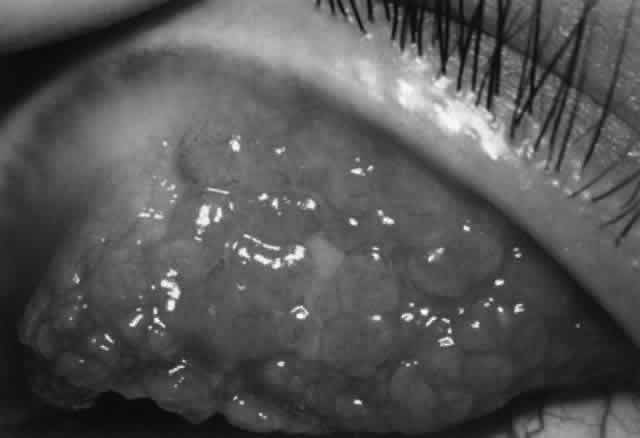

Rao and associates127 described the histopathologic features of necrotizing scleritis secondary to rheumatoid arthritis and other systemic autoimmune diseases versus idiopathic necrotizing scleritis. The former group showed granulomatous inflammation, ischemic necrosis, and vasculitis, whereas the idiopathic group showed predominantly a nongranulomatous chronic inflammation without vasculitis. Rao and colleagues127 concluded that the immunopathogenesis of necrotizing scleritis related to rheumatoid arthritis and other connective tissue diseases is an immune complex-mediated vasculitis, whereas that for idiopathic necrotizing scleritis is more consistent with a delayed-type hypersensitivity reaction.

More recently, Fong and co-workers128 have described immunopathologic studies that suggest that necrotizing scleritis represents an immune complex-mediated vasculitis combined with T-cell mechanisms. On histopathologic examination of conjunctival and scleral biopsies in patients with non-necrotizing and necrotizing scleritis, Fong and colleagues demonstrated granulomatous inflammation consisting of histiocytes, plasma cells, and giant cells in the sclera surrounded by chronic inflammatory cells in the overlying episcleral and conjunctival layers. Vasculitis with fibrinoid necrosis and cellular infiltration of the vascular wall was present in both sclera and conjunctiva. More important, by using immunohistochemical techniques, they demonstrated immunodeposits in scleral and conjunctival vessel walls in the majority of samples (IgM, IgD, IgA, C3, and C4 being most commonly identified). Conjunctival epithelium and substantia propria contained significantly increased numbers of T cells, macrophages, and B cells. The sclera itself contained large numbers of T cells (both suppressor/cytotoxic T cells and helper T cells) and macrophages. Both conjunctiva and sclera showed increased HLA-DR expression over controls. Circulating immune complexes were also demonstrated in about 80% of patients.

These findings support the concept of an immune complex-mediated (type III) vasculitis in the etiology of scleritis combined with concurrent significant involvement of T-cell mechanisms undoubtedly leading to a granulomatous response.128

CORNEAL GRAFT REJECTION